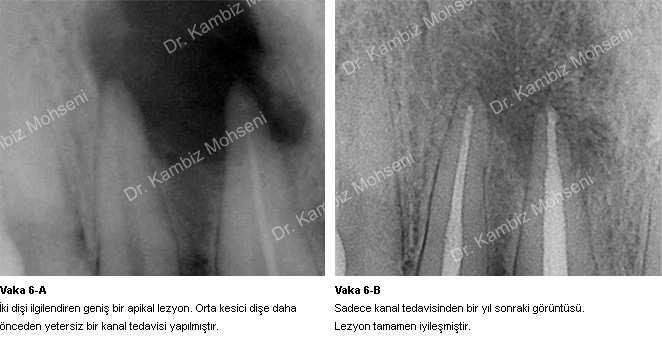

İltihabın sebebi kök kanal sistemindeki mikroorganizmalardır. Uygun bir kanal tedavisi ile ortam mikroorganizmalardan arındırılırsa iltihabın iyileşme şansı oldukça yüksektir. Bu konuyla ilgili örnek vakaları inceleyebilirsiniz;

Vaka 2-A, 2-B, 4-A, 4-B ve 5-A, 5-B.

Eğer daha önceki tedavi başarısız olmuşsa sebep araştırılmalıdır. Malesef gördüğümüz başarısız kanal tedavilerinin çoğu yetersiz şekillendirme, temizlik ve doldurmadan kaynaklanmaktadır. Bu durumda eğer dişte kalıcı hasar meydana gelmemişse kanal tedavisi yenilenebilir. Bu işleme “retreatment” yada “kanal tedavisi tekrarı” denir.

Vaka 3-A, 3-B ve 6-A, 6-B.

Diş ağrısı kanal tedavisi endikasyonu için önemli bir kriterdir. Kendiliğinden veya ağrı kesici kullanılmasına rağmen geçmeyen ağrılar dişin artık kendini savunamadığını gösterir. Bu durumlarda kanal tedavisi gerekir. Bazı kronik durumlarda dişte herhangi bir rahatsızlık olmamasına rağmen yapılan radyografik kontrollerde kökte iltihaplanmalara rastlanabilir. Bu durumlarda da kanal tedavisi gerekir. Dişe önceden yapılan yetersiz kanal tedavileri yeniden yapılan düzgün bir kanal tedavisi ile daha uzun süre ağızda kalabilir.